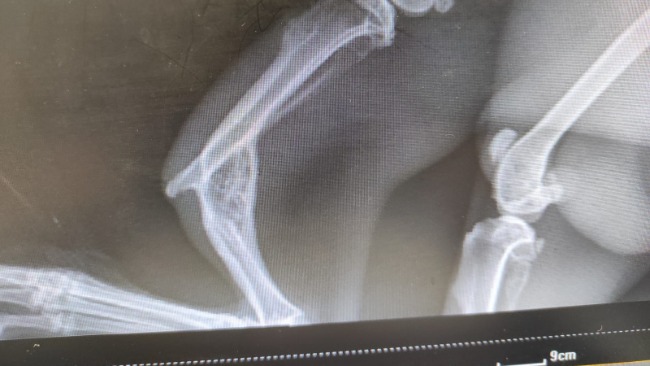

Percy - chłopczyk ze starym, już zrośniętym w nieodpowiedni sposób, złamaniem podudzia. Prawdopodobnie po złamaniu nie została mu udzielona pomoc. Jak bolało to wie tylko on. Kończyna nie funkcjonuje prawidłowo, ale maluch zdaje się tego nie zauważać. Niezwykle odważny i proludzki.